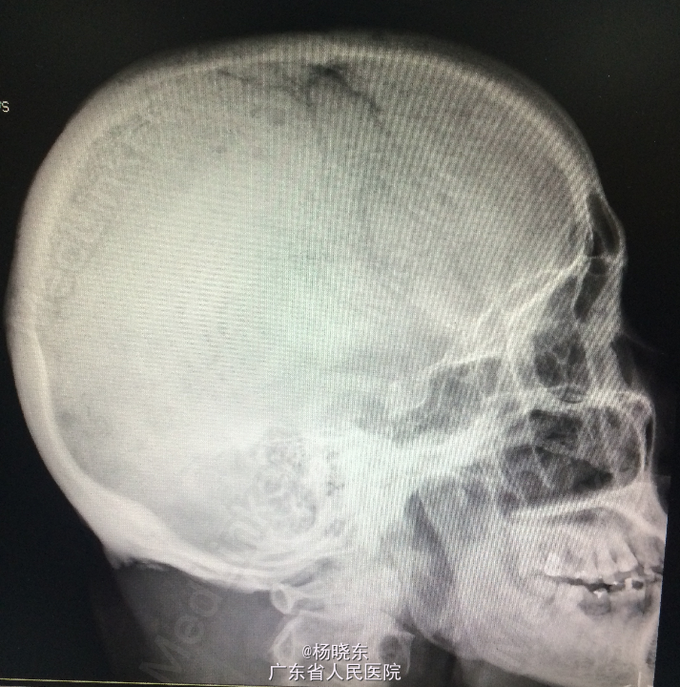

查体:贫血貌,心肺腹查体无特殊。 辅查: 1.全长双下肢长骨正位+尾椎正侧位+肋骨正位+右关节正位+骨盆正位+腰椎正侧位+下胸椎正侧位放射常规照片示:考虑多发性骨髓瘤(多发骨病变)。1、颈椎退行性变 2、腰椎退行性变;多个椎间盘病变;L1椎体轻度压缩性骨折。3、胸椎退行性变。 2.骨髓活检:可见少许造血成分,粒红比例大致正常,均以中晚幼阶段细胞为主,全片可见三个巨核细胞,形态未见明显异常。并可见浆细胞散在。 3.骨髓-外周血涂片:MM-骨髓增生活跃,浆细胞占58.0%,其中原幼浆占53.5%,外周血占2.0%。